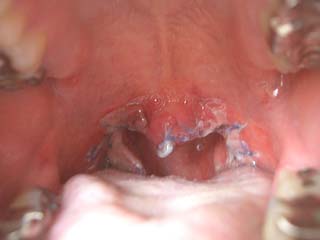

|

術後二日目。周りに白いものができてきた。

どうやら「かさぶた」らしいです。 |